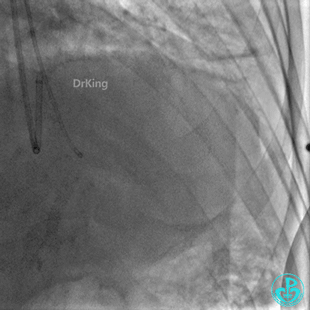

前降支末梢经微导管释放3.0×2.5mm弹簧圈封堵破口。

明胶在血管怎么降解并发症丨前降支CTO同侧逆向开通时侧支血管破裂,弹簧圈联合明胶海绵封堵_https://www.jmylbn.com_新闻资讯_第33张

钝缘支经微导管释放5.0×5.5mm弹簧圈封堵破口。

明胶在血管怎么降解并发症丨前降支CTO同侧逆向开通时侧支血管破裂,弹簧圈联合明胶海绵封堵_https://www.jmylbn.com_新闻资讯_第34张

明胶在血管怎么降解并发症丨前降支CTO同侧逆向开通时侧支血管破裂,弹簧圈联合明胶海绵封堵_https://www.jmylbn.com_新闻资讯_第35张

双向弹簧圈封堵后观察30分钟,病情稳定,渗漏似乎减少,返回病房。